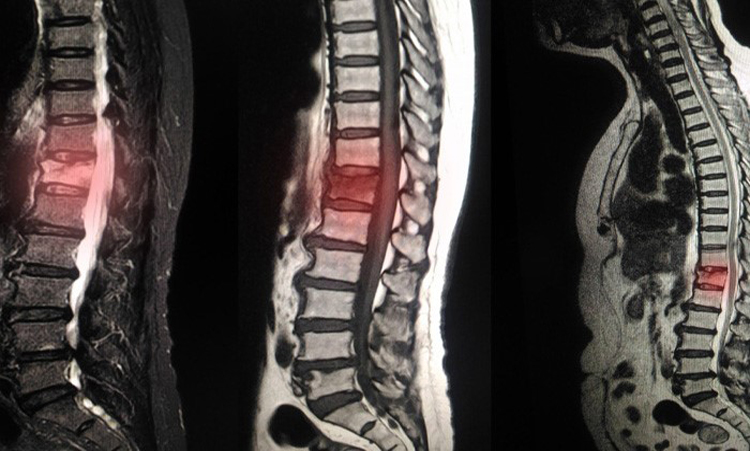

خواندن تصاویر ام آر آی نیاز به درک عمیق از آناتومی ستون فقرات و دیسکهای بینمهرهای دارد. تصاویر ام آر آی معمولاً به صورت مقاطع افقی، عمودی یا مایل از ناحیه کمر ارائه میشوند. در هر تصویر، پزشک باید به دنبال تغییرات غیرطبیعی در بافتها، مانند ورم، هرنی دیسک یا تغییرات دژنراتیو باشد. آشنایی با ساختارهای آناتومیکی، مانند مهرهها، دیسکها و عصبها، به پزشکان کمک میکند تا تغییرات را بهتر شناسایی کنند.

در تفسیر تصاویر ام آر آی، پزشکان باید به جزئیات دقیق توجه کنند. به عنوان مثال، در هرنی دیسک، ممکن است بخشهایی از دیسک به سمت خارج فشار بیاورند که میتواند به عصبها آسیب بزند. این نوع تغییرات در تصاویر به صورت برجستگی یا افتادگی دیسک مشاهده میشود. همچنین، علائم دیگری مانند تنگی کانال نخاعی، که ممکن است به دلیل بزرگ شدن لیگامانها یا دیسکها ایجاد شود، باید در نظر گرفته شوند. شناخت این علائم و نشانهها برای تشخیص صحیح ضروری است.